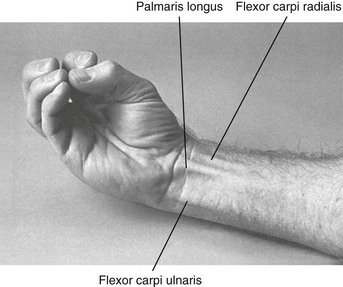

Анатомия мышцы Palmaris Longus